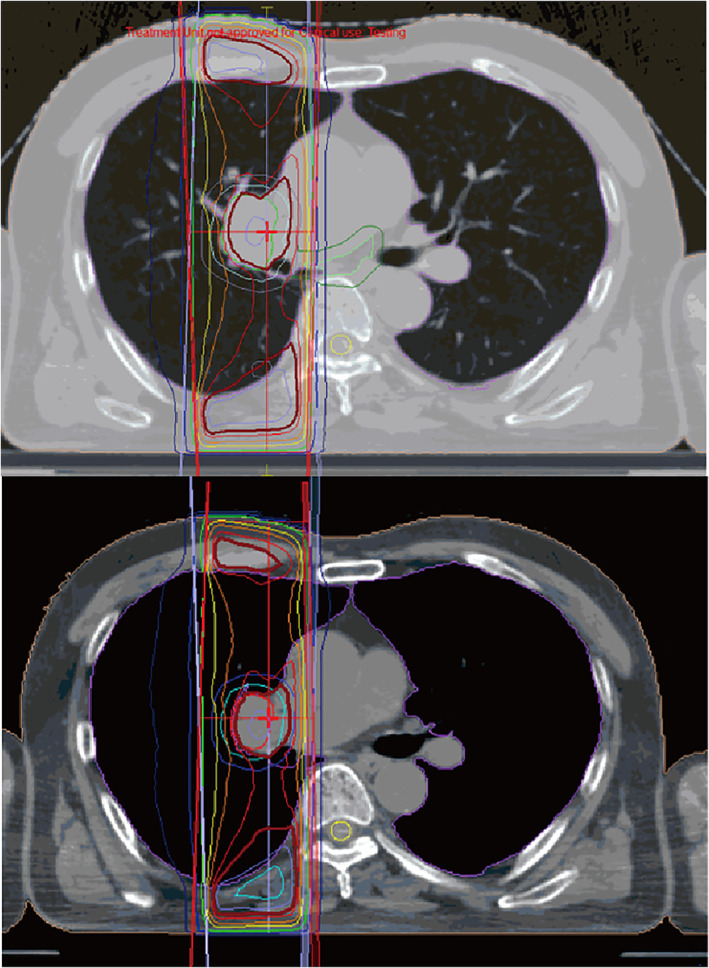

A 60‐year‐old‐man with locally advanced NCSLC (cT3N1M0, stage IIIA) underwent concurrent chemoradiotherapy. He was treated with two cycles of cisplatin (60 mg/m2) plus tegafur‐gimeracil‐oteracil (120 mg/day) in combination with concurrent radiotherapy (60 Gy/30 fr). Irradiation was designed as shown in Figure 1. The irradiation area was close to the spinal cord, which might be associated with the myelosuppression. Although grade 3 neutropenia and thrombocytopenia required dose reduction in the second course, he completed the chemoradiotherapy. However, maintenance therapy with durvalumab was postponed owing to the sustained thrombocytopenia. He had not had hematologic diseases in the past. He had not taken any causal medication. Coagulation test showed hyperfibrinolysis through the entire course. A month later, durvalumab was initiated as the platelet count recovered to 142 × 103/μL (Figure 2(a)). Soon after durvalumab was initiated, thrombocytopenia emerged at a minimum level of 55 × 103/μL despite normal hemoglobin concentration and white cell counts. Durvalumab was discontinued after five cycles because thrombocytopenia did not ameliorate. Because the level of platelet‐associated IgG (PA‐IgG) was approximately twice as much as the normal level, bone marrow examination was conducted. The bone marrow was normoplastic and the pathology did not demonstrate cancer invasion, blastic proliferation, myelodysplasia, or myelofibrosis. Only the megakaryocyte depletion was demonstrated (Figure 3), which was inconsistent with that of idiopathic thrombocytopenic purpura (ITP). There were few platelets surrounding the megakaryocyte. In the bone marrow smear, nucleated cell counts were 56 000/μL, which indicated slight hypoplasia. The myeloid:erythroid (M:E) ratio was 1.48. The proportion of myeloid, erythroid, and lymphoid series were 53.2%, 32.6%, and 12.8%, respectively. We had not performed the bone marrow biopsy. He was treated with 30 mg of prednisolone, which was gradually tapered to 10 mg (Figure 2(b)). Six months later, the platelet counts recovered to the level of 110 × 103/μL.

FIGURE 1.

The design of irradiation. The irradiation area was close to the spinal cord